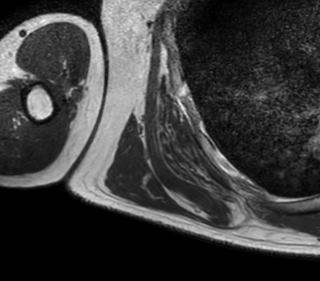

背部弾性線維腫とは、肩甲骨の下側内側にできる、痛みの少ない良性のこぶです。中高年、特に55歳以上の女性に多く、沖縄の離島でよく見られます。肩甲骨と胸壁の間で、繰り返される摩擦や圧力が原因で、線維と脂肪が層のように重なったような組織ができると考えられています。MRIでは筋肉と同じ濃さに見えながら、中にレース状の脂肪が混じる特徴的な模様が現れます。大きくなっても動かしにくくなることは少なく、痛みがなければそのまま様子を見ます。悪性にはならず、自然に消えることもありませんが、放置しても問題ない病気です。

触診、CT、MRI、超音波断層撮影で肩甲骨に接するような腫瘤を認めます。発生する場所や腫瘤の形態から診断します。MRIの所見は筋肉とおなじ吸収域を示し、内部に脂肪が混在します。